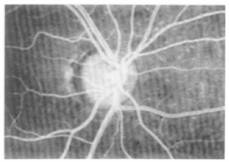

The application of RTD analysis in bio medical engineering is being used at an increasing rate. For example Professor Bob Langer's1 group at MIT used RTD analysis for a novel Taylor-Couette flow device for blood detoxification while Lee et al2 used an RTD analysis to study arterial blood flow in the eye. In this later study sodium fluorescence was injected into the anti-cubical vein. The cumulative distribution function F(t) is shown schematically in Figure 13.5.N-1. Figure 13.5N-2 shows laser ophthalmoscope image after injection of the sodium fluorescence. The mean residence time can be calculated for each artery to estimate the mean circulation time (ca. 2.85 seconds). Changes in the retinal blood flow may provide important decision making information for sickle cell disease and retinitis pigmentosa.

Figure 13.5.N-2 Image of eye after tracer injection. Courtesy of Med. Eng. Phys.2 |